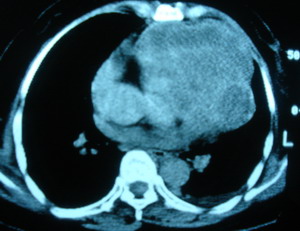

心包內惡性畸胎瘤X光圖早期病人無明顯臨床症狀,不易診斷。如出現胸部不適或心前區刺痛,心電圖僅提示心率異常無特異性。普通胸片檢查常因腫瘤與心臟影像重疊可造成漏診或誤診。近年來影像學發展迅速,現代化的高科技影像設備和技術已經成為心包內畸胎瘤診斷的主要檢查手段超聲心動描記或攝影心血管螢光電影照像術以及放射性核素掃描等綜合檢查,可以發現心包內腫塊的密實影像或回聲以及大量的心包腔積液。計算機中軸體層攝影(CT)對不同密度的組織如脂肪、水軟組織、骨骼的高解析度使心包內畸胎瘤的術前診斷成為可能磁共振成像(MRI),利用心血管中血液的流空效應也對本病的診斷很有意義。